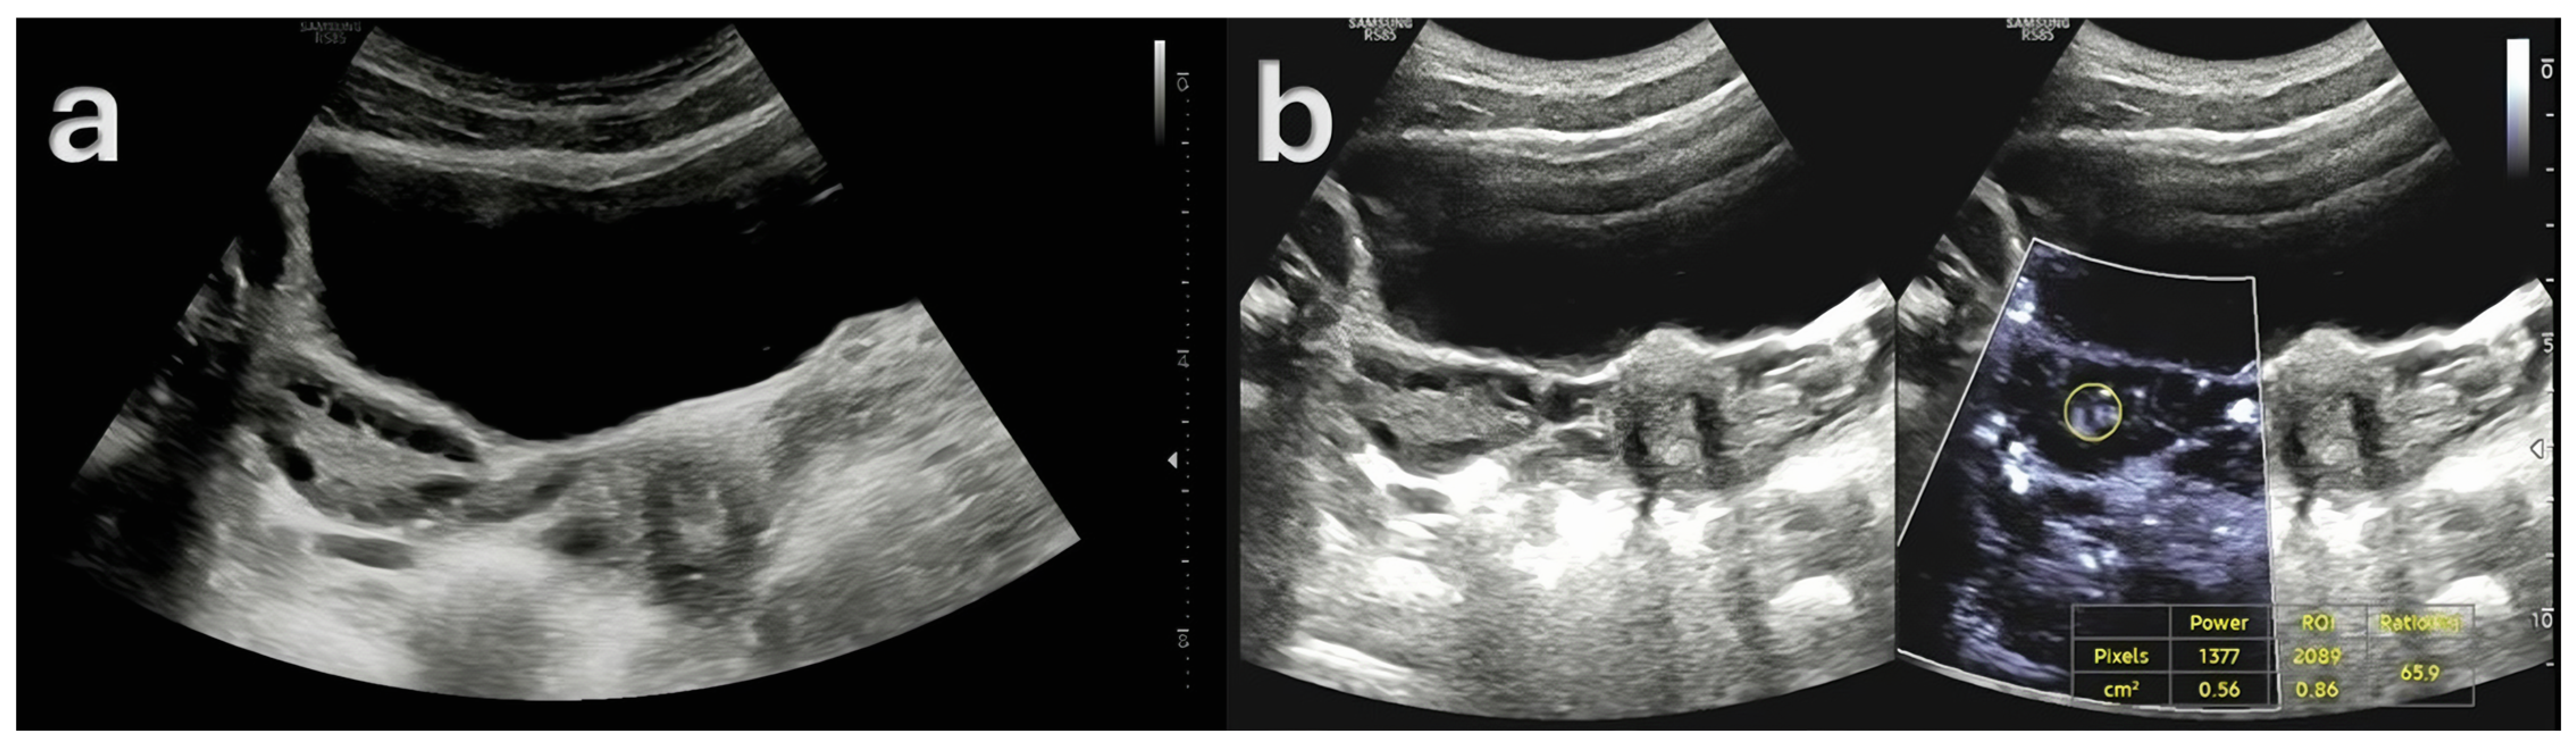

- Doppler Examination (MV-Flow, MVI): Ovarian stromal vascularity was evaluated using the same ultrasound equipment and transducer (Samsung RS85 Prestige with CA1-7A, 1–7 MHz). MV-Flow Doppler imaging was performed consistently in the longitudinal plane to maintain anatomical standardization. Cine-loop clips of at least 3 s duration were captured and stored. For vascularity index measurements, the optimal frame demonstrating clear vascular flow was selected from the stored cine-loop clips. In the ovarian stroma, three circular regions of interest (ROIs) were centrally positioned. These ROIs, each with a fixed 5 mm diameter, were carefully selected to exclude dominant follicles and peripheral vascular structures. The ROI dimensions and MV-Flow Doppler imaging parameters, including pulse repetition frequency (PRF), gain, and wall filter, were maintained consistently throughout the duration of the study.